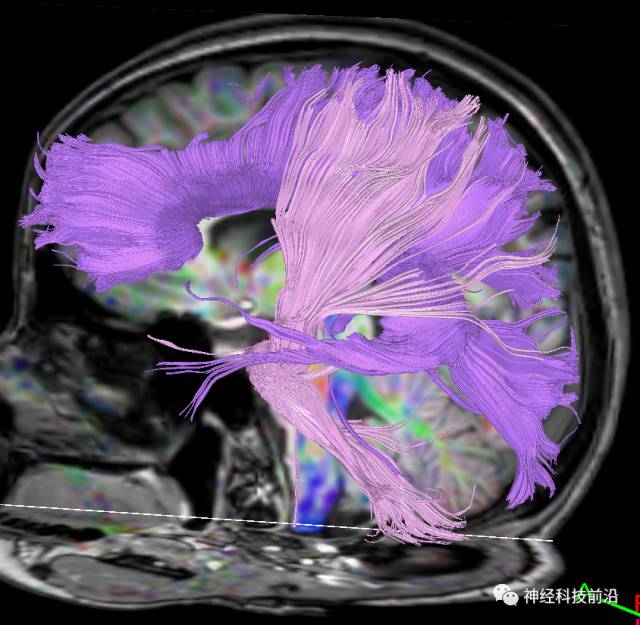

下面为皮质脊髓束的走形及位置

下面为皮质脑桥束的走形方位

皮质脊髓束与皮质脑桥束的关系毗邻

终上所述:脑干高信号为一近环形纤维束,内囊后肢高信号为皮质脑桥束,皮质脊髓束在中脑位置略靠后。高信号位于中脑前缘,是皮质脑桥束的位置所在,另外有部分桥连纤维。